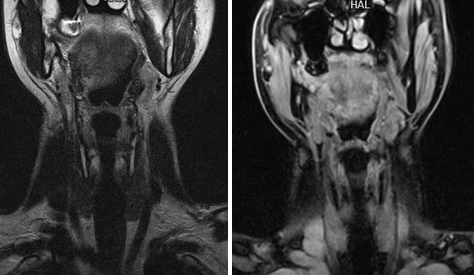

Рисунок 1,2. МРТ мягких тканей шеи (Т2-ВИ и Т1-fs-ВИ контрастное усиление). Патологических образований в структуры щитовидной железы не выявлено.